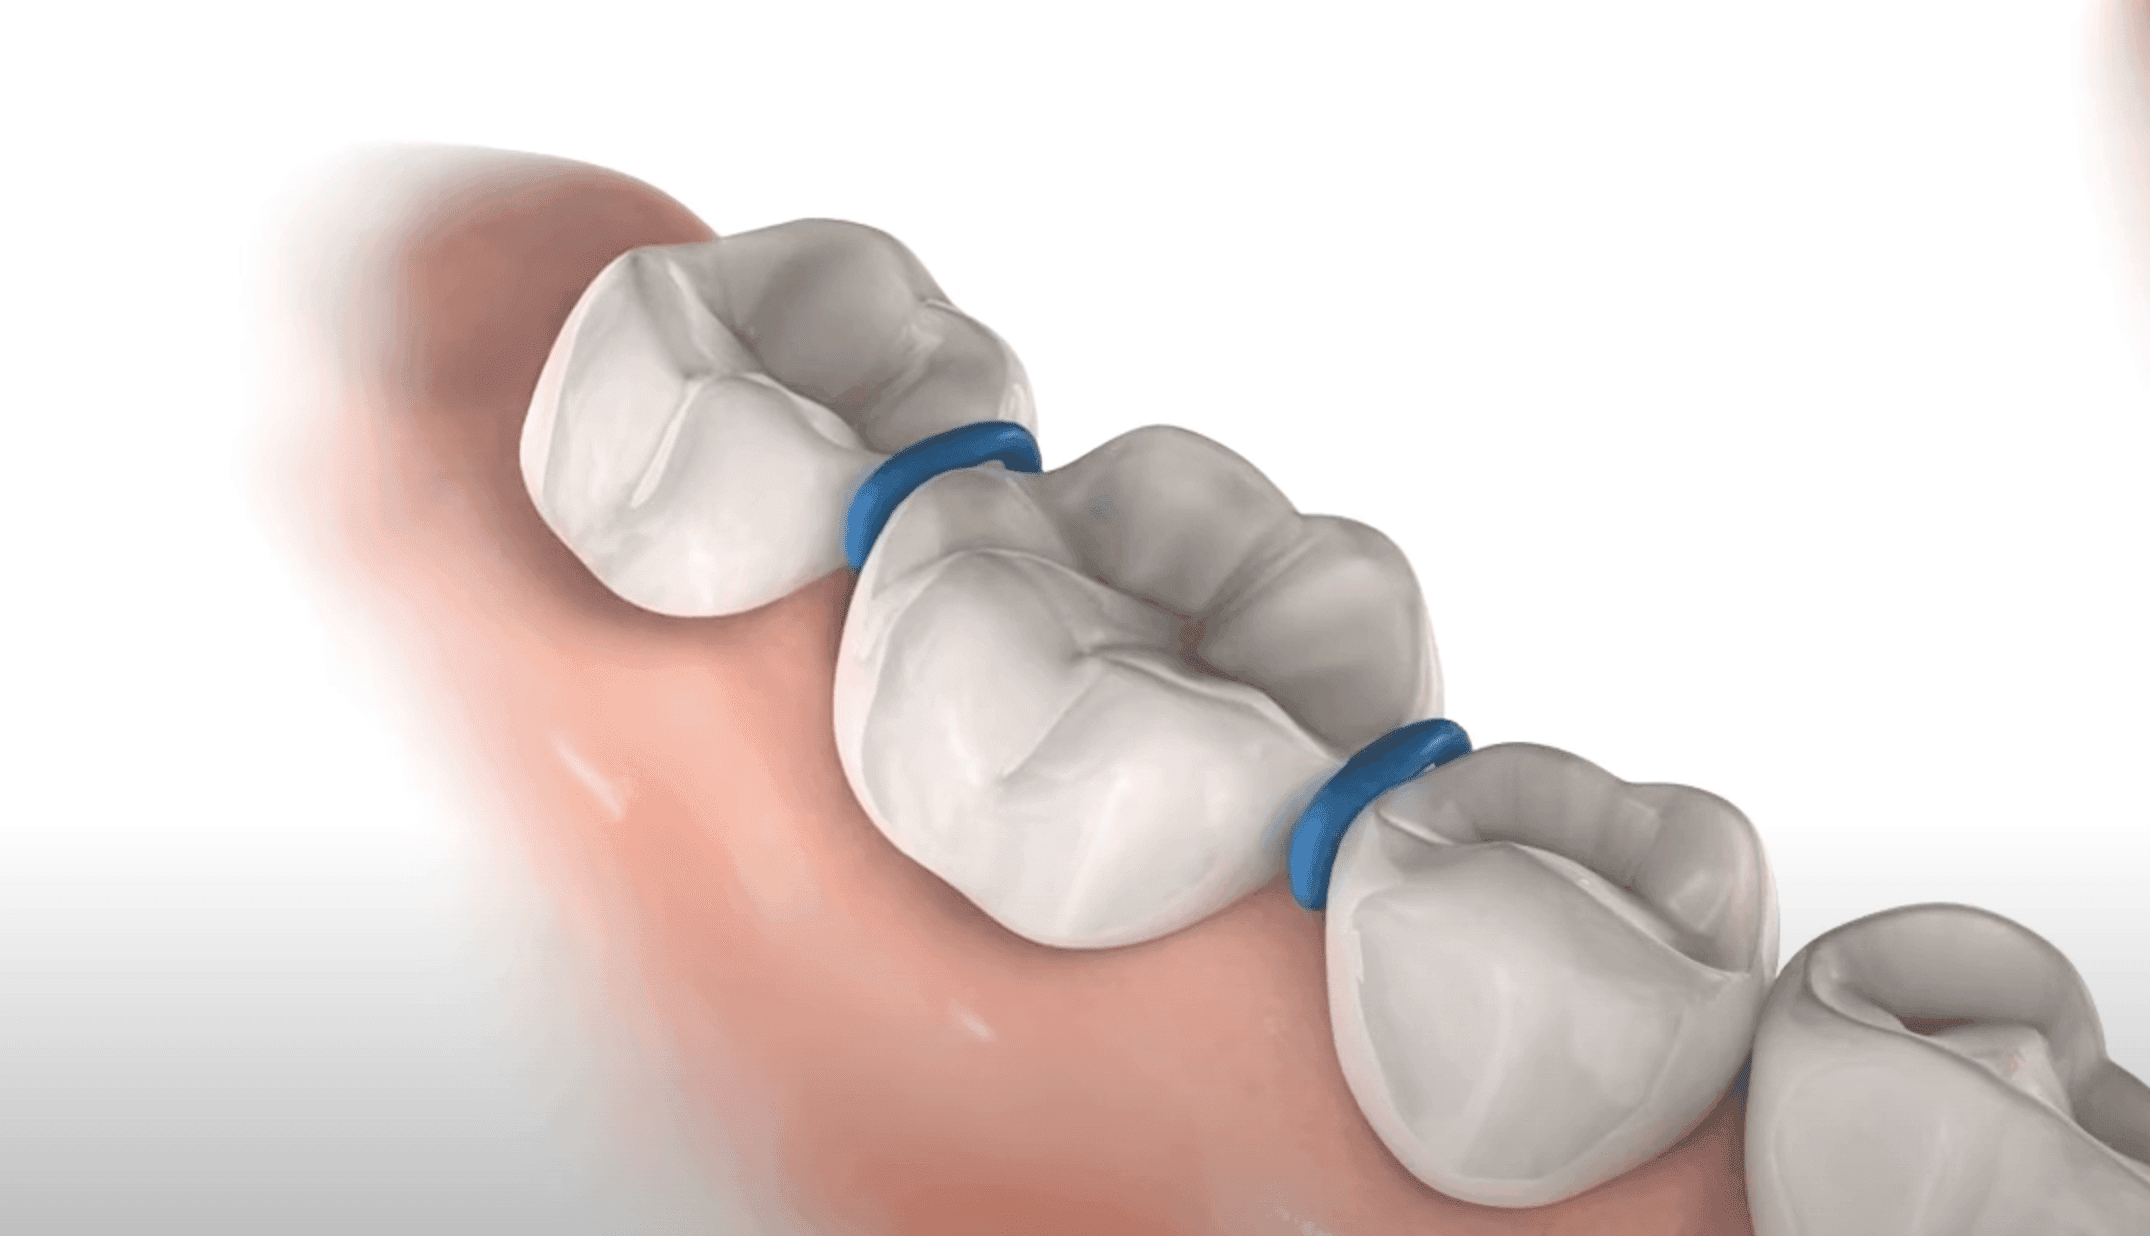

We doen meestal maar een kroon per keer, we hebben hier de beste ervaring mee. We hebben twee zittingen nodig:

Plaatsen stiekjes naast de kies, 5 min werk.

Passen en plaatsen kinderkroon. Ook een korte ronde, 5-20 min max, 2 dagen na de stiekjes.